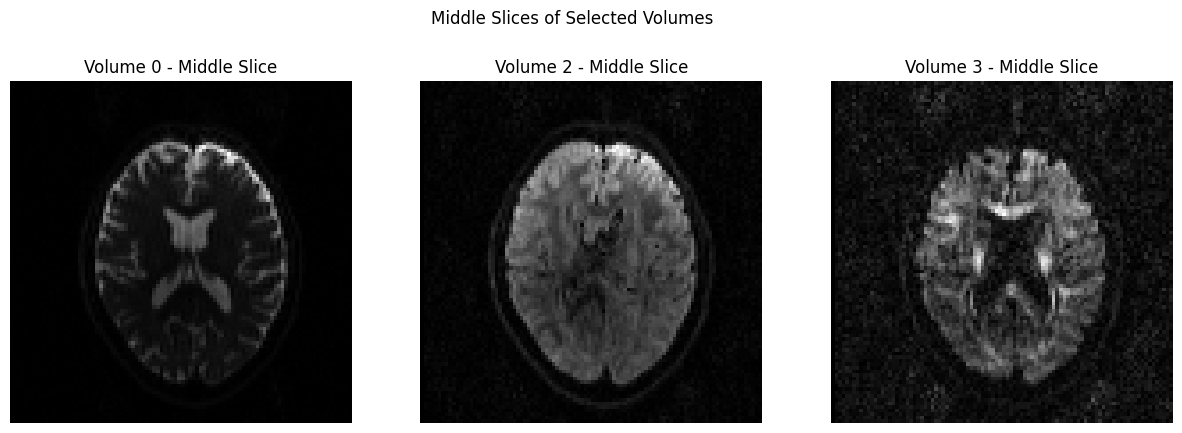

In order to view the image, we will use a couple of different packages, and you can determine which one you prefer. The first one we will use it matplotlib

, which was loaded earlier in this notebook. In the code below, we will temporarily convert the data to NIFTI format and plot 3 volumes with Matplotlib.

dwi_file = 'sub-CON02_ses-preop_acq-AP_dwi.nii.gz'

volume_indices = [0, 2, 3]

slice_index = data.shape[2] // 2 # Choose the middle slice for visualization

fig, axes = plt.subplots(1, 3, figsize=(15, 5))

for i, vol_idx in enumerate(volume_indices):

# Extract the middle slice from the selected volume and rotate it 90°

rotated_slice = np.rot90(data[:, :, slice_index, vol_idx])

axes[i].imshow(rotated_slice, cmap="gray")

axes[i].set_title(f"Volume {vol_idx} - Middle Slice")

axes[i].axis("off")

plt.suptitle("Middle Slices of Selected Volumes")

plt.show()

Another way to view these images is through nilearn, which contains a plotting library. The code below will import the necessary packages, and then extract and plot the first volume of the time-series. This opens an interactive plot upon which you can click and drag your mouse cursor. Note in particular that the frontal pole is slightly deformed and squished inwards; we will fix that by using topup

.